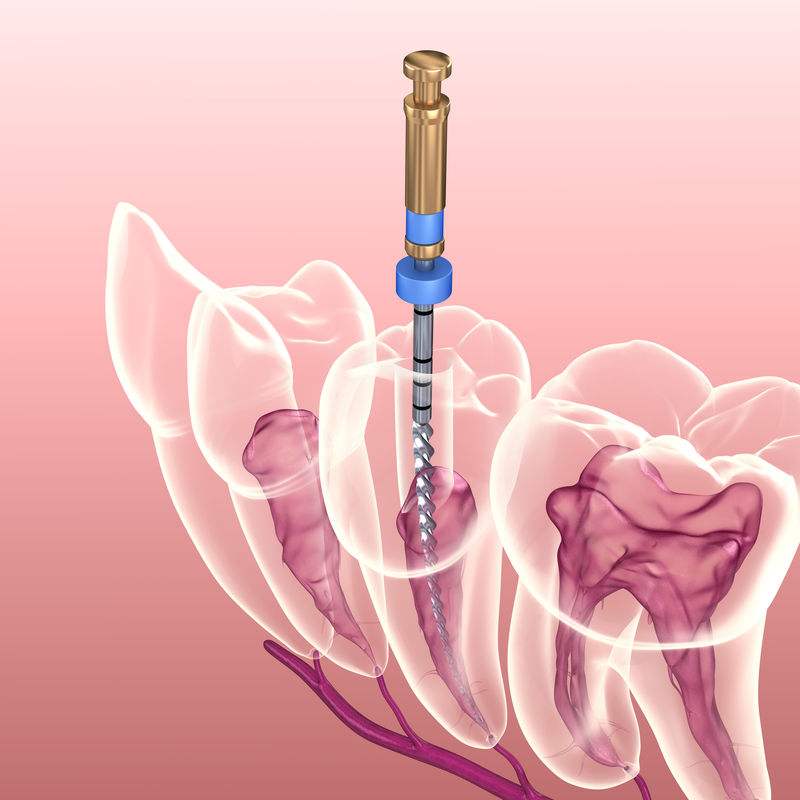

牙齿根管治疗又称为牙髓治疗,根管治疗适应范围较广,牙髓炎,牙髓坏死,各种类型的根尖周炎都适于作根管治疗,包括由于龋齿、隐裂、过度消耗、穿髓等引起的牙髓坏死不能保留... 详情

单纯用材料已经无法恢复功能 因为需要进行根管治疗的牙齿,一般已经是蛀牙缺损很大,这个时候虽然根管治疗完成,但是剩下的牙体组织很少,单纯用材料已经没法补牢实,易脱落。... 详情